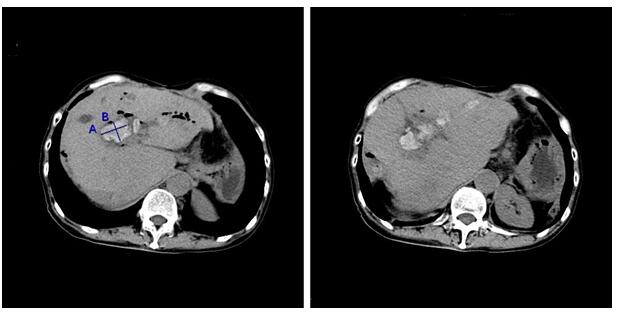

更不幸的是,今年年初,周某复查发现肝内胆管结石又复发了。周某采用保守消炎治疗,短短半年时间,反复寒战,发烧,肚子痛5次,并且眼睛和皮肤越来越黄。为求治疗收入我院。入院后完善腹部CT检查,发现周某肝内胆管又长了许多结石,主要集中在肝门胆肠吻合口附近和左边肝内胆管,导致肝内胆管明显扩张(见图1)。当我们和周某商量下一步治疗方案的时候,周某说自己做了4次开刀手术,非常惧怕再次开刀。我们深表同情,有没有办法不开刀,肚子上打个小洞就能取出肝内胆管的结石呢?

图1患者术前CT检查。肝内胆管多发结石(已标记),最大直径约3厘米,肝内胆管扩张和积气。